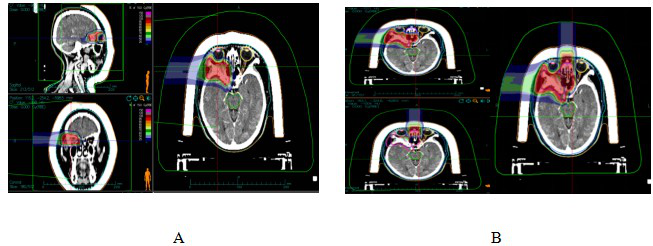

Case 1: Female, 44 years old, squamous carcinoma of the right lacrimal sac. She visited our hospital in July 2022, and on examination, she was found to have a swelling of about 3 cm × 4 cm in size in the lower eyelid of her right eye, with mild limitation of eye movement in all directions. After a thorough examination and evaluation of the patient, the patient was treated on 20 July 2022 with CIRT. The prescribed dose for the first course: PTV 40Gy (RBE)/10fx; lateral position, 2D homogeneous scanning, and the dose distribution is shown in Figure 1A.The prescribed dose for the second course: PTVboost 24Gy (RBE)/6fx; supine position, 2D homogeneous scanning. The total dose to the tumour area was 64 Gy (RBE)/16 F, 4.0 Gy (RBE)/F, and 5 F/w, and the dose distribution is shown in Fig. 1B.Comparison of the dose distribution of axial images between CIRT and volume-modulated intensity-adjusted radiotherapy (VMAT) plans while both fulfilling the prescriptive requirements, and the range of the surrounding normal tissues irradiated at low doses was significantly smaller for the CIRT plan compared to the VMAT plan, see Fig. 2A and The efficacy of CIRT was compared by imaging data before and after treatment, and the patient's efficacy was assessed according to the Response to Evaluation Criteria for the Evaluation of Solid Tumours (RECIST) 1.1, and the efficacy of treatment reached a complete remission (CR) 3 months after treatment, as shown in Fig. 3. During the CIRT treatment period and in the first month after the treatment, the patient developed grade 1 acute radiation conjunctival injury; 3 months after the end of radiotherapy, she developed dry eyes, and the use of eye drops for a long time was considered to be grade 1 radiation conjunctival damage, which was considered to be grade 1 radiation conjunctival damage. , considered grade 1 radiation conjunctival injury (RTOG Acute Radiation Injury Grades), no late adverse events greater than grade 2 were observed.Combination of a target (cetuximab) during CIRT treatment, with disseminated rash on the face during the treatment period, grade 1 on the Common Terminology Evaluation Criteria for Adverse Events. As of September 2024, the patient is currently disease-free and continues to be followed for the long term.

Figure 1 CIRT dose distribution in patients with dacryocystosquamous cell carcinoma

Note: Figure 1A: One course CIRT dose distribution. Figure 1B: Two course CIRT dose distribution

Figure 2 VMAT plan and carbon ion plan dose distribution in patients with dacryocystosquamous cell carcinoma

Note: Figure 2A: VMAT plan dose distribution in patients with dacryocystosquamous cell carcinoma. Figure 2B: Carbon ion plan dose distribution in patients with dacryocystosquamous cell carcinoma.